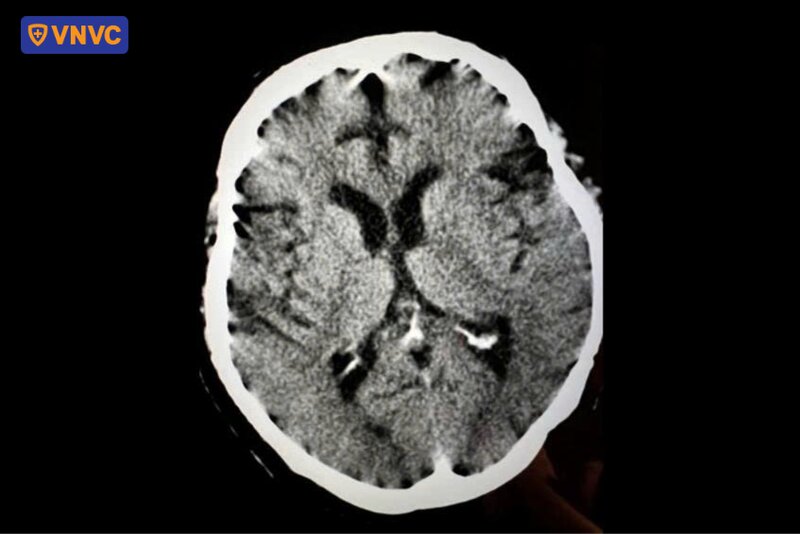

Trường hợp ông Bùi Thịnh (61 tuổi, Hà Nội) là một minh chứng điển hình cho mức độ nguy hiểm của các biến chứng này. Thông tin từ Bệnh viện Đa khoa Tâm Anh Hà Nội, ông Thịnh nhập viện trong tình trạng sốt cao liên tục, đau đầu dữ dội, méo miệng, mắt nhắm không kín, đau rát họng và khó nuốt. Vùng miệng, họng và tai phải của bệnh nhân xuất hiện nhiều vết loét, kèm các nốt mụn nước và mủ rải rác trên thân mình. Kết quả xét nghiệm và chẩn đoán hình ảnh xác định bệnh nhân mắc zona lan tỏa biến chứng viêm màng não, liệt dây thần kinh VII ngoại biên và nhiễm khuẩn huyết.

Ở một số trường hợp, VZV xâm nhập sâu vào hệ thần kinh trung ương, di chuyển dọc theo các dây thần kinh cảm giác đến vùng đầu hoặc tủy sống. Khi tái hoạt động, virus nhân lên và phá hủy tế bào thần kinh, đồng thời kích thích phản ứng viêm mạnh trong cơ thể. Phản ứng viêm này khiến màng não bị sưng và tổn thương, người bệnh xuất hiện sốt cao, đau đầu dữ dội, buồn nôn, rối loạn ý thức, cứng gáy thậm chí co giật hoặc hôn mê.